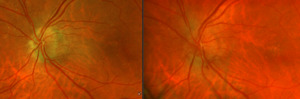

After additional testing was completed, and comparison of previous photos were conducted, it was determined that the patient had not only optic disc drusen, but also possible bilateral amiodarone optic neuropathy. The photos 4 months apart shows increasing pallor in the left eye and a blood vessel at 7 o’clock that did not look obscured initially but was evidently more pronounced on the follow up when comparing the initial and follow-up photos. This shows the importance of quality serial fundus photography.

Right image is original exam with inferior hemorrhage. Left image is 4-month follow-up visit. Resolution of the hemorrhage is seen, but atrophy of the disc overall should be noted. Vessel at 7 o’clock should also be noted. It appears much more pronounced than on initial visit.